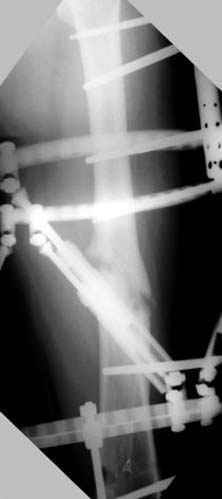

пластическая модель; и коррекция бедра аппаратом Илизарова.

Имею другие снимки тоже, получится как отчет о моей работе.

Узкий к-м канал - тонкий гвоздь- усталостный перелом дистальных винтов - развитие нестабильности и как ее результат остеолиз вокруг гвоздя - деформация анатомической оси бедра. Похоже, что я понял почему аппарат, а не новый гвоздь:-)

ЕТ - Изначально костно-мозговой канал бедра был узкий, дальнейшее его рассверливание ещё больше скомпрометирует прочность бедра( латеральный кортекс дистального отломка уже истончен), приведет к дефекту наружной стенки - хотя это только мои догадки - хотелось бы знать мнение Джолдаса о выбранной тактике.